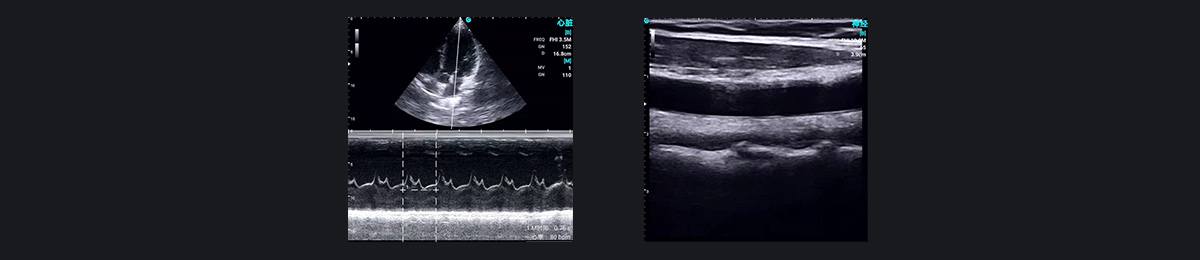

SonoEye 演示图像:术前和术后护理

除了神经阻滞之外,超声对于评估循环量和监测围手术期状态也具有无价的价值。它的应用减少了患者伤害并改善了整体体验,显着影响了心脏手术和危重患者的麻醉管理。

SonoEye 手持式超声波提供一系列探头,涵盖全面的身体扫描。高频线性探头提供出色的二维成像,清晰显示针路,而彩色模式有效显示血流,帮助麻醉医生识别主要血管,避免意外穿刺。 SonoEye设备符合军用级IP67防尘防水标准,可在无菌手术室环境中进行彻底的浸泡消毒,从而防止交叉感染。